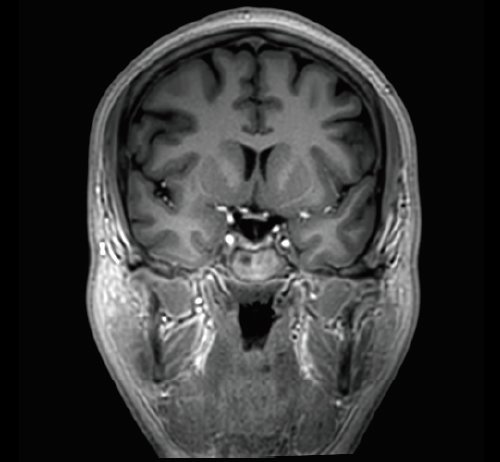

Der Vantage Galan 3T von Canon Medical Systems bietet Ihnen und Ihren Patienten eine neuartige Erfahrung in der Magnetresonanztomographie. Der Vantage Galan 3T legt sein Augenmerk auf das positive Patientenerlebnis, eine hohe Bildqualität und einfache klinische Arbeitsabläufe.

KI-optimiertes Arbeiten und modernste 3T-Technologie machen den Vantage Galan 3T von Canon Medical aus. Canons KI-Anwendung AiCE, kurz für Advanced intelligent Clear-Imagequality Engine, entfernt intelligent das Rauschen und führt zu einer Verbesserung des SNR (Signal-Rausch-Verhältnis). Mit Hilfe der Deep Learning Technologie gelingen besonders klare und deutliche Bilder. Insgesamt ermöglicht die KI-Unterstützung des Vantage Galan 3T somit nicht nur eine höhere Auflösung der Bilder, sondern verkürzt in vielen Fällen auch die Aufnahmezeit.

Auch das Patientenwohl kommt bei dem Vantage Galan 3T nicht zu kurz. Der kurze Magnet wird ergänzt durch eine 71cm weite Patientenöffnung. Ein helles und modernes Design lässt den MRT weniger bedrohlich wirken. Die Pianissimo Technik verringert die Geräuschbelastung während der Untersuchung signifikant und MR Theater trägt durch visuelle Eindrücke zur Entspannung des Patienten bei.